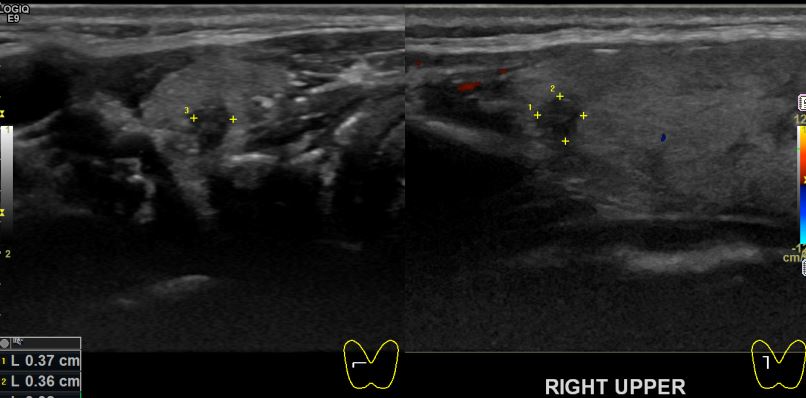

아산유외과개원후 47번째 갑상선암진단

상기환자 30대 여성분으로 검진시 우측 의심스러운혹

세포검사진행후 갑상선암으로 진단되었습니다